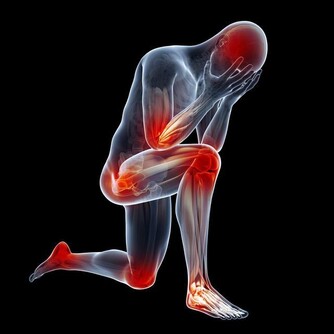

大部分肝癌患者到了晚期都會有很明顯的疼痛感,而早期很少有疼痛情況出現,一般出現明顯的疼痛都已發展到中晚期了,但是有疼痛并不代表就是肝癌,需要分清楚是哪裡疼痛,然後再進行針對性的檢查。

這種疼痛比較常見,在溫度發生變化或者勞累的情況下也會出現,一般進行合適的休息會自行緩解。而肝癌導致的腰背部的疼痛是因為受到腫瘤的壓迫,腫瘤壓迫神經、肌肉,從而出現腰背部疼痛的現象。

肝癌會轉移到其他部位,比如轉移到肺部、骨骼處、那麼就可能出現骨痛、胸痛的情況。